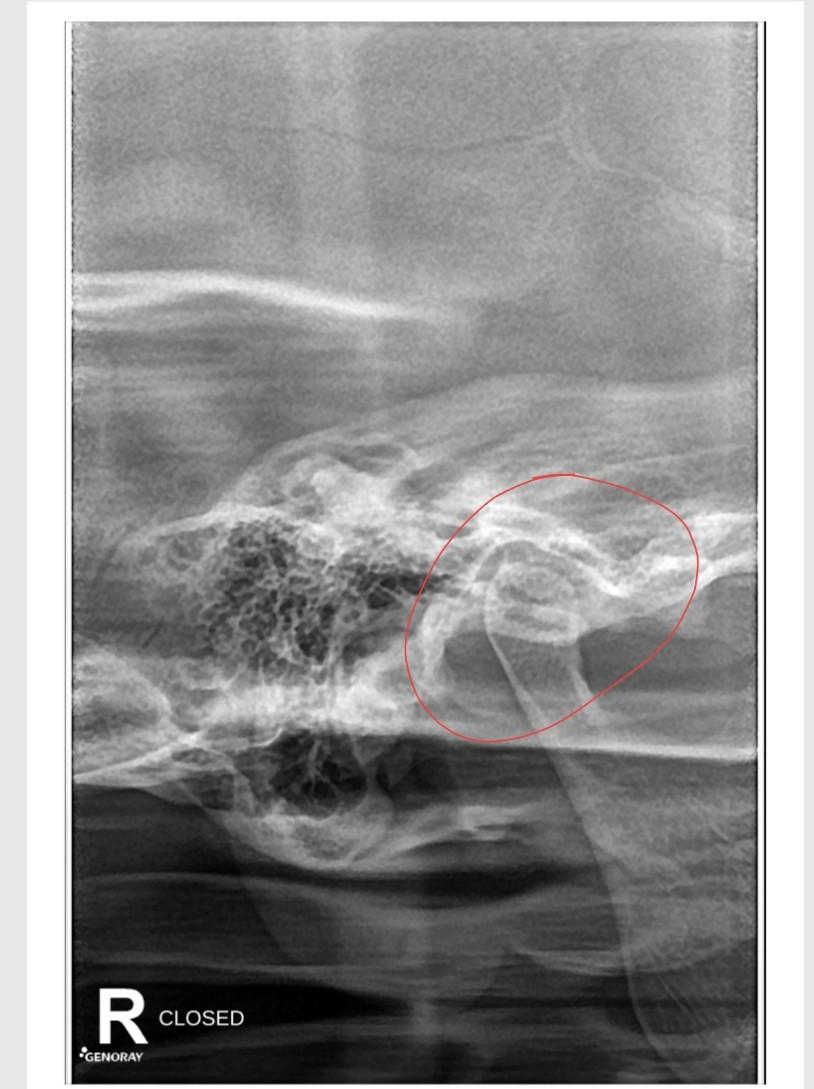

Condylar Fracture